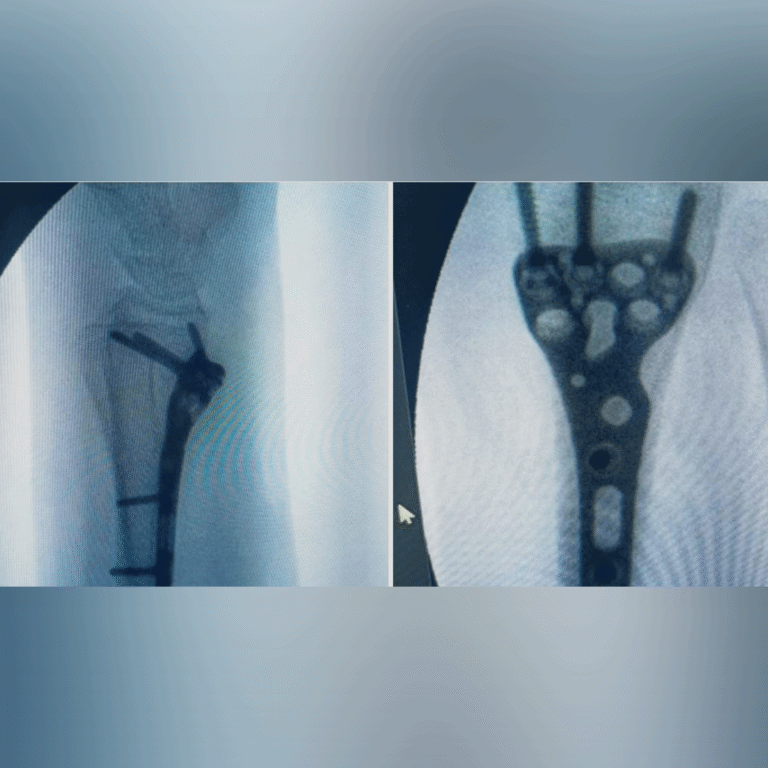

🩺 Resultados que transforman vidas. Descubre cómo hemos devuelto la movilidad y eliminado el dolor de mis pacientes mediante tratamientos efectivos.